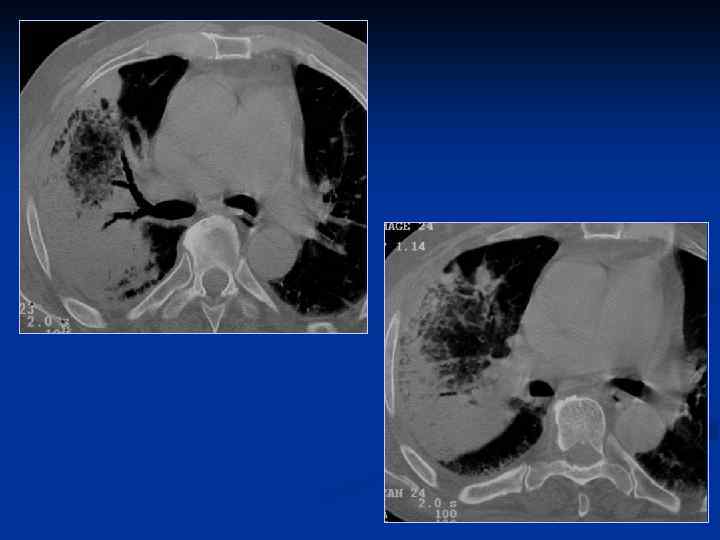

КТ–семиотика плевропневмонии – прямые признаки n n Уплотнение легочной ткани Симптом «воздушной бронхографии» Уменьшение объема Плевральные изменения

Плевропневмония

ПН верхней доли. Микс – флора: в S 3 – классические признаки в S 2 - признаки нагноения